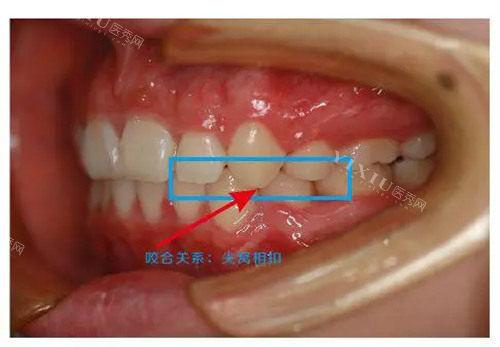

在技术方面,植得口腔的特色在于其多样化的种植方案,能够针对不同患者的牙槽骨条件、咬合关系等个性化因素,提供定制化的治疗计划。